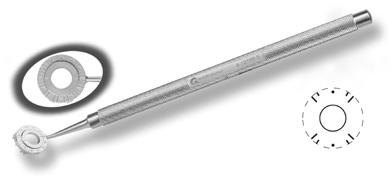

disruption, but may mask an unintentional perforation. The extent of arc to be incised may be demarcated in several different

ways. Our preferred method makes use of a modified Fine-Thornton fixation

ring (Nichamin Fixation Ring and Gauge; Mastel Precision, Storz, Rhein

Medical). This instrument serves to fixate and position

the globe in order to optimize incision placement, as well as to delineate

the extent of arc to be incised. One visually extrapolates from

the limbus to marks on the surface of the ring. Each incremental mark

is 10 degrees apart, and bold hash marks (180 degrees) opposite

to each other serve to align and center the incision over the steep

meridian. This approach obviates the need to ink and physically mark

the cornea. If one desires, particularly when first gaining experience

with LRIs, a two-cut RK marker may be used to place ink marks upon the

cornea to show the exact extent of arc that is to be incised, in conjunction

with the fixation ring/gauge (Fig. 4). Alternatively, various press-on markers are available, such as

markers, rings, and blades for performing LRIs.  Fig. 4. The Nichamin Fixation Ring and Gauge serves to both fixate the globe and

delineate the extent of arc to be incised; a two-cut radial marker may

be used to mark the extent of arc to be incised, and the Mastel Nichamin

Force AK Diamond Blade with preset depth of 600 microns. Fig. 4. The Nichamin Fixation Ring and Gauge serves to both fixate the globe and

delineate the extent of arc to be incised; a two-cut radial marker may

be used to mark the extent of arc to be incised, and the Mastel Nichamin

Force AK Diamond Blade with preset depth of 600 microns.